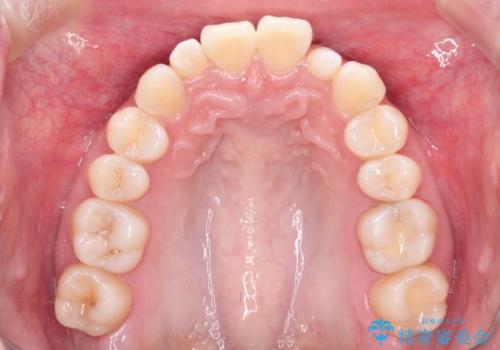

上顎の歯が全体的に前方に位置しているのと、前から2番目の歯が通常よりも小さい矮小歯という状態でした。

出っ歯をなおすために上顎の前から4番目の歯を抜歯して、引っ込めるのと、前から2番目の歯に通常の大きさのオールセラミックを装着して整った歯並びにすることにしました。

歯の大きさが通常と異なる場合は矯正治療で歯並びだけきれいにしても、整わないことがあります。

その場合はセラミックのかぶせ物を装着して歯の形を正常にすることで、さらに整った歯並びにすることができます。